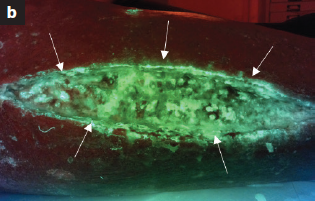

Diagnosis and treatment of the invasive extension of bacteria (cellulitis) from chronic wounds utilizing point-of-care fluorescence imaging

Andersen, A. et al. Int Wound J 2021